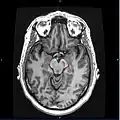

Horizontal MRI (T1 weighted) slice with highlighting indicating location of the substantia nigra. -